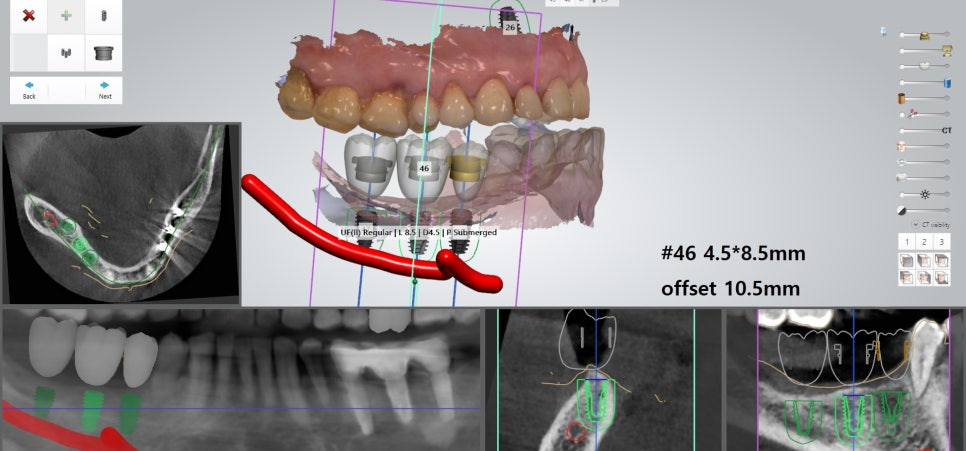

‘내비게이션 모의수술 프로그램’을 통해

치료 계획을 수립할 수 있겠습니다.

특히 아래에 지나가는

하치조 신경을 유의해야 됩니다.

왼쪽, 오른쪽 모두

아래턱 쪽으로 하치조 신경이 지나갑니다.

각 부위에 다수의 치아를 식립하게 될 경우

더욱이 심어야 될 위치나 깊이를

자세히 체크할 필요 있습니다.

디지털 시스템,

오차 범위를 줄이는 방식

픽스처의 식립 각도나 위치가 중요하기 때문에

치조골 상태에 따라 계획이 달라질 수 있는데

이를 보완하기 위해 내비게이션 시스템은

3D CT와 구강 스캐너를 활용해

사전에 정밀하게 계획을 세우고 진행됩니다.